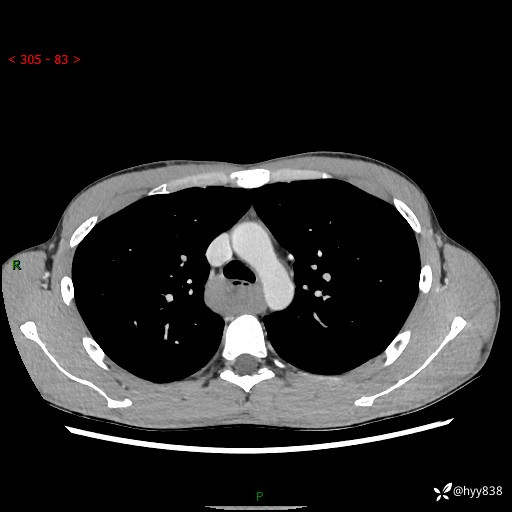

年轻男性,发现后纵隔占位1周余。征象简单,难在定位---结果公布~

现病史:患者于1周前体检行检查发现后纵隔占位,患者平素无明显咳嗽咳痰,无心慌、胸闷、胸痛、呼吸困难、低热、盗汗,无头痛、头晕,无腹痛、腹胀等不适。现患者欲求进一步治疗,遂来我院就诊,以“纵隔占位”收入我科。 患者自起病以来,精神可,睡眠可,饮食可,大小便正常,体重无明显改变。

胸部CT平扫+增强